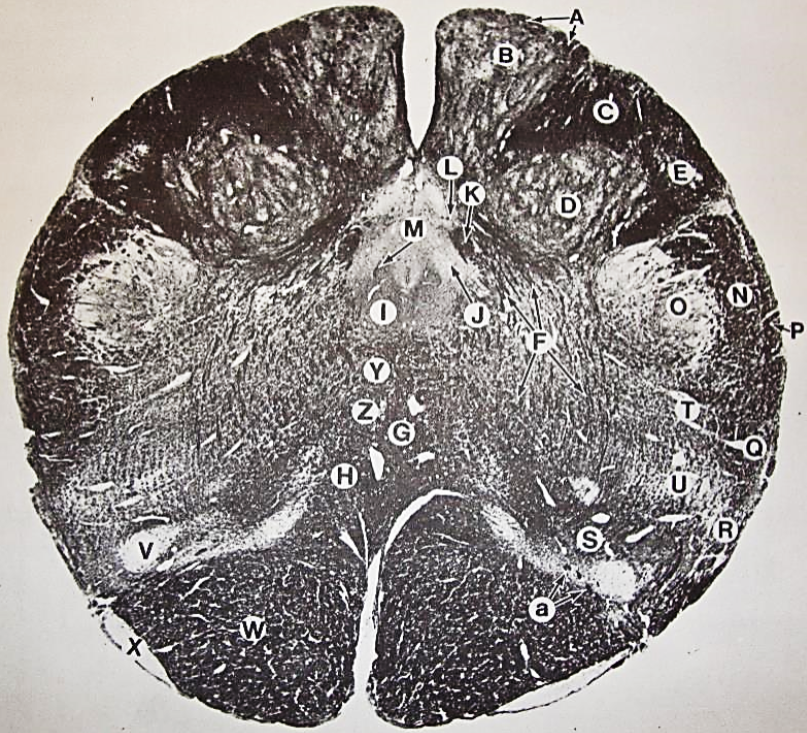

A

Fasciculus gracilis

B

gracile nucleus

C

fasciculus cuneatus

D

cuneate nucleus

E

spinal trigeminal tract

F+G collectively

spinal trigeminal nucleus

H

accessory nucleus

I

pyramidal decussation

J

rubrospinal tract

K

posterior spinocerebellar tract

L

anterior spinocerebellar tract

M

lateral spinothalamic tract

N

anterior spinothalamic tract

O

lateral vestibulospinal tract

P

medial longitudinal fasciculus

Q

tectospinal tract